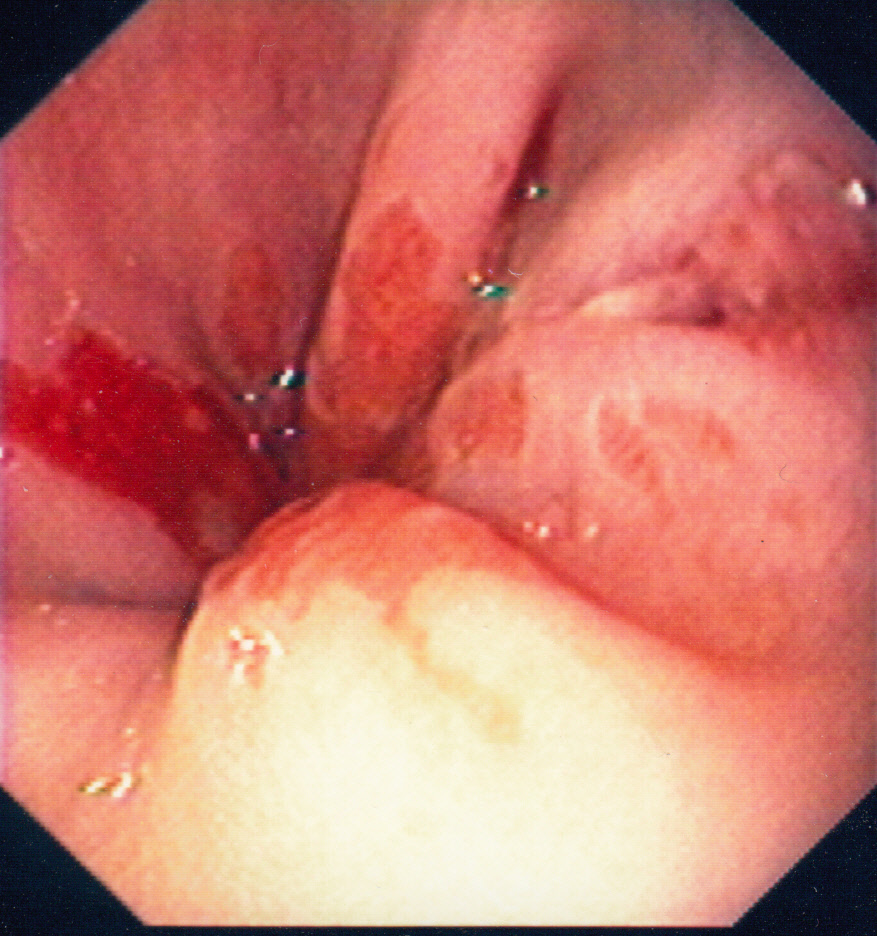

Mallory Weiss-tear

Mallory–Weiss syndrome or gastro-esophageal laceration syndrome refers to bleeding from a laceration in the mucosa at the junction of the stomach and esophagus. This is usually caused by severe vomiting because of alcoholism or bulimia,[1] but can be caused by any conditions which causes violent vomiting and retching such as food poisoning. The syndrome presents with hematemesis. The laceration is sometimes referred to as a Mallory-Weiss tear. (Source: Wikipedia)